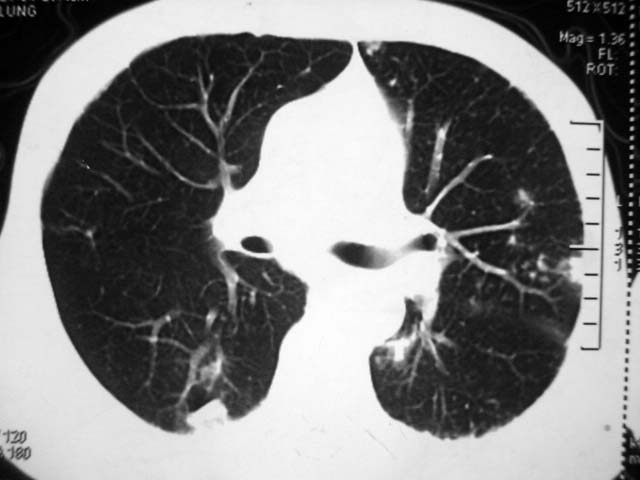

男,52岁,发热2月,糖尿病史。

抗结核治疗irpz方案,血糖未治疗,空腹15.9左右。症状无好转,左胸痛。

复查ct

2、双肺见多发片状及结节状高密度影,大多数病灶中心均见“空泡征”。

3、纵隔内淋巴结肿大。

结果:两肺继发性肺结核并曲霉菌感染。